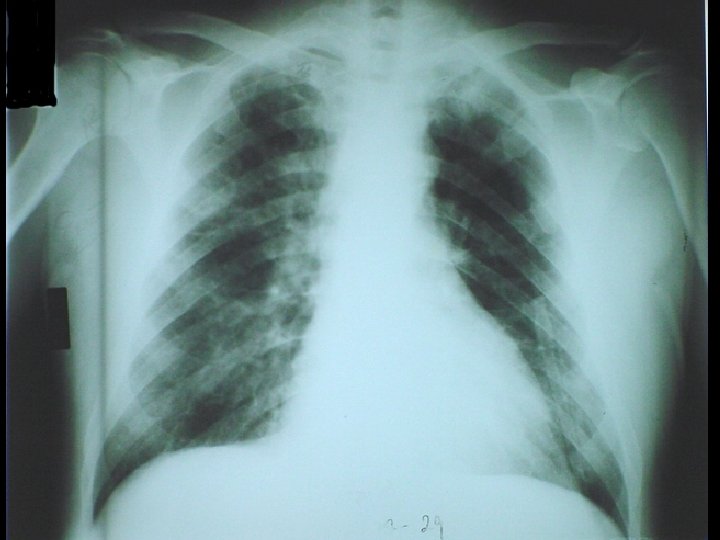

WEGENER’S GRANULOMATOSIS * An uncommon pulmonary-renal disease * Characterized by granulomatous inflammation, necrosis and vasculitis primarily in URT, LRT and kidneys * Pathophysiology • Autoantibodies to proteinase-3 in neutrophil granules • Proteinase-3 translocates to surface following activation of neutrophils * Etiology is unknown and no genetic predispostion * Laboratory diagnosis • Antineutrophil cytoplasmic autoantibodies (ANCA) • Biopsy of lung and kidney

GOODPASTURE'S SYNDROME * An uncommon pulmonary-renal syndrome * Characterized by pulmonary hemorrhage and glomerulonephritis * Pathophysiology • Antibodies to type IV collagen in alveolar and glomerular basement membranes * Laboratory diagnosis • Anti-GBM (Ig. G to glomerular basement membrane) • Biopsy of lung and kidney